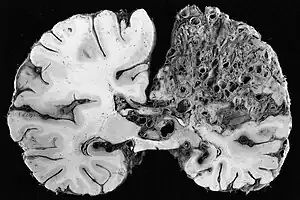

vein of Galen malformation -

Vein of Galen thrombosis from ventricular puncture, not to be mistaken for an aneurysmal malformation